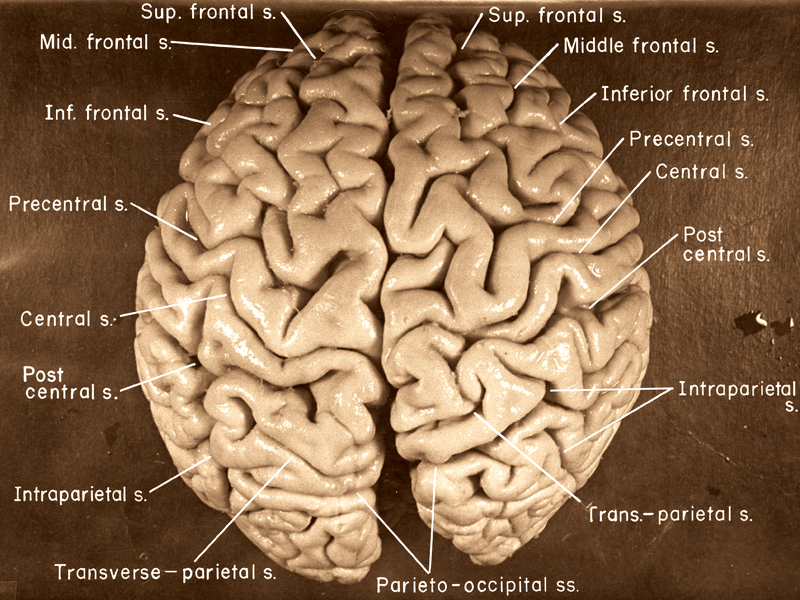

Https www alamy com a specimen of nobel physicist albert einsteins brain is seen in a glass slide at an exhibition at the wellcome collection in london march 27 2012 weve pickled it dessicated it drilled it mummified it chopped it and sliced it over centuries yet as the most complex entity in the known universe the human brain remains a mysterious fascination with samples of albert einsteins preserved brain on slides and specimens from other famous and infamous heads such as the english mathematician charles babbage and notorious mass murderer william burke an exhibition opening in london this week image377121679 html (Dateityp jpg)

Einsteins Brain High Resolution Stock Photography And Images Alamy